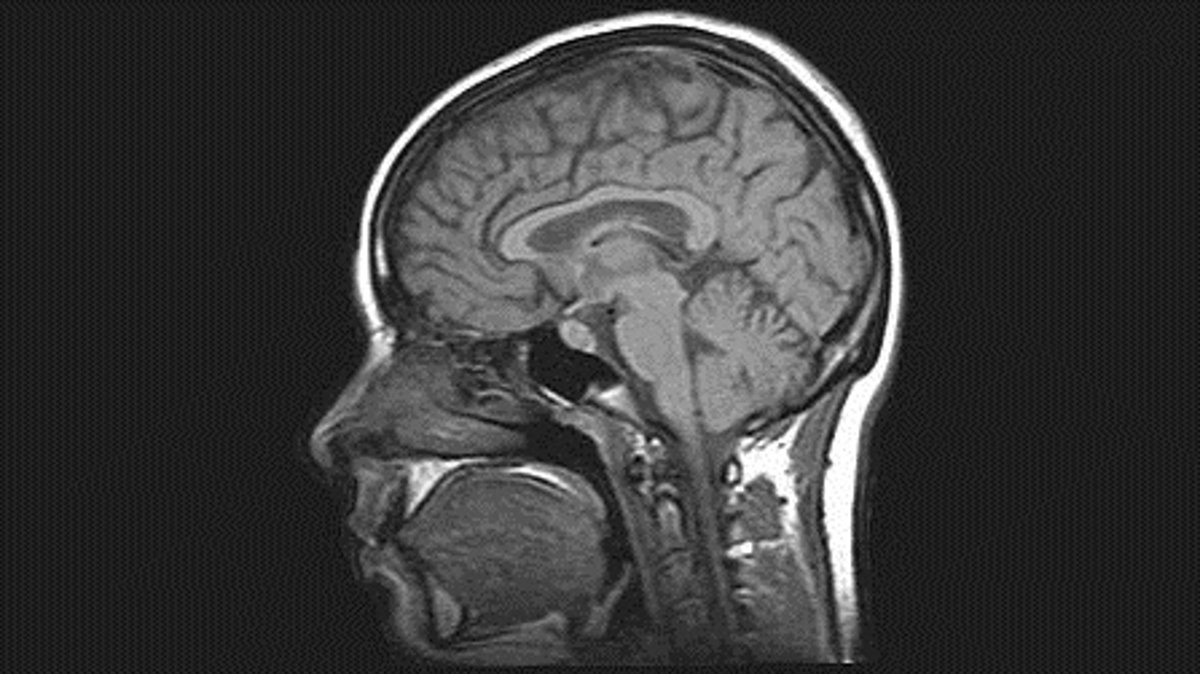

Cerebro humano

WIKIMEDIA COMMONS

Para ello, la herramienta utiliza rutinas espaciales para analizar las imágenes de resonancia magnética (IRMs), gracias a la experiencia adquirida por Deimos para la ESA al desarrollar rutinas de 'software' que permiten analizar las imágenes por satélite, buscando patrones e identificando elementos específicos.

Los científicos de Deimos utilizan AlzTools para analizar los datos tomados por un escáner cerebral, en vez de un satélite de observación de la Tierra. En lugar de una cosecha o de una carretera, analizan zonas del cerebro como el hipocampo, cuya atrofia está relacionada con el Alzheimer.